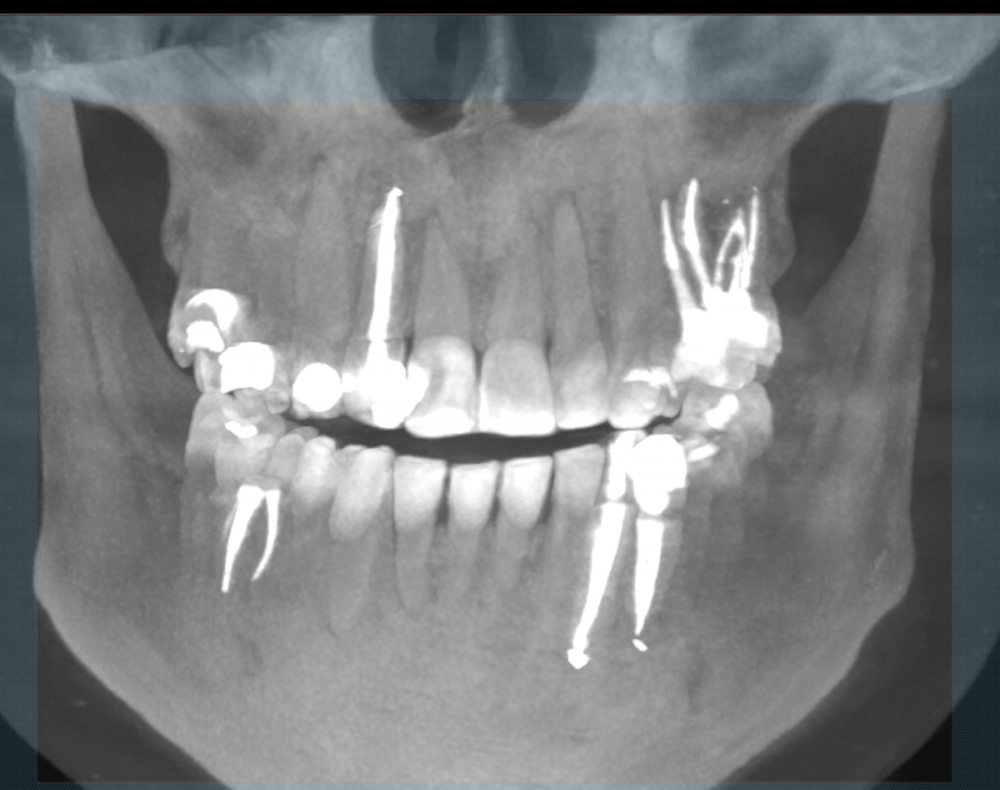

sewif Опубликовано 5 июня, 2020 Автор Поделиться Опубликовано 5 июня, 2020 (изменено) ЗдравствуйтеСегодня сделал контрольное КТ. После лечения прошло где-то 5-5,5 месяцев. КТ делал в одной клинике, а доктор который лечит зубы работает в другой клинике (к нему визит послезавтра) . В клинике в которой делал КТ, работает ЧЛХ из Моники, я к нему сразу на консультацию и записался. Мнение хирурга:1) По верхней кисте заметная положительная динамика.2) По нижней кисте: непонятно. Далее пишу сумбурно, в голове каша но как я понял: похоже на то, что жидкость из кисты ушла. Киста "скукожилась" и что-то в ней образовалось (непонятно что..фиброз? или что-то другое). Также сказала, чтобы врач внимательно посмотрел 5 зуб...возможно его стоит тоже депульпировать.Вердикт: ждать еще 3 месяца. Также сказала, что если бы она не видела снимок от октября 2019г...то по текущему снимку, сказала бы что у меня не кисты, а другие болячки с зубами....по нижней амеоба-чего-то там Первый снимок от 24 октября 2019Второй снимок от 05 июня 2020 Изменено 5 июня, 2020 пользователем sewif Ссылка на комментарий

Irouil Опубликовано 5 июня, 2020 Поделиться Опубликовано 5 июня, 2020 Есть положительная динамика и наверху, и внизу Ссылка на комментарий

Bier Опубликовано 5 июня, 2020 Поделиться Опубликовано 5 июня, 2020 на мой взгляд явное улучшение и вверху и внизу Ссылка на комментарий